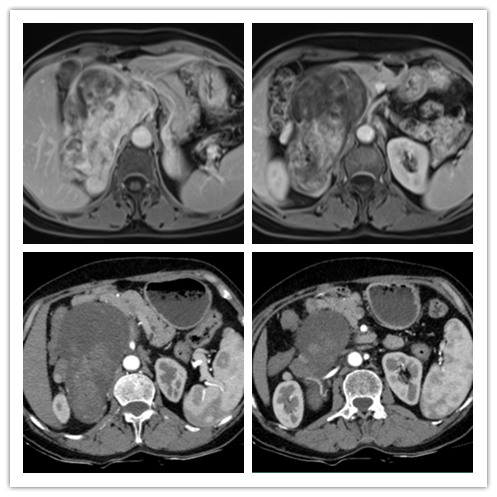

患者一,女性,62岁。因“体检发现右侧肾上腺区占位10余天”入院。入院后完善相关检查及化验,其中RAAS系统化验正常,尿液中香草扁桃酸及游离肾上腺素升高3倍,CT提示右侧肾上腺区混杂密度占位性病变,内可见结节状钙化灶,大小约129*97*98mm,下腔静脉受压向前向外侧偏移,邻近脏器受压改变,增强扫描未见明显不均匀强化。MR显示右侧肾上腺区占位病变,合并囊性变、坏死、出血,多考虑恶性肿瘤性病变,嗜铬细胞瘤恶变多考虑并右肾动静脉、下腔静脉、邻近脏器受压移位,胸部CT及全身骨显像未见明显转移灶,术前诊断为腹膜后肿瘤。泌尿外科在充分做好术前准备后,为患者实施开放腹膜后肿瘤切除术,最终完整切除肿瘤及肾上腺,手术历时约3小时,患者术后恢复良好,术后病检提示嗜铬细胞瘤。